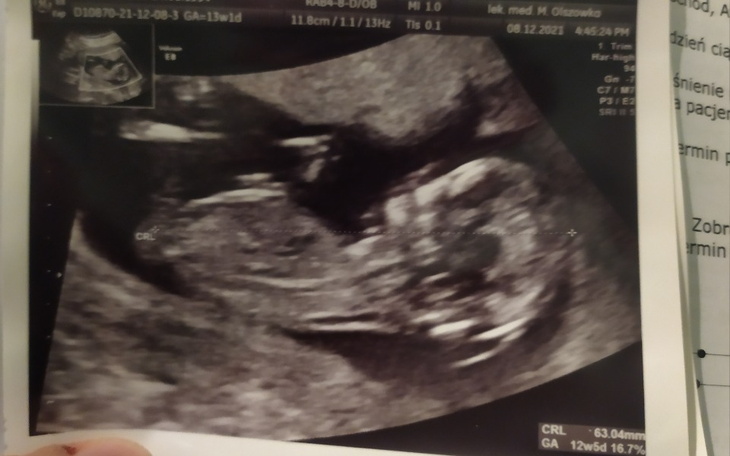

Wraz z mężem zbieramy na wyprawkę dla dziecka. Mas stracił pracę zaraz po tym jak okazało się że jestem w ciąży. Utrzymujemy się głównie z mojej wypłaty. A do spłacenia mamy kredyt z wesela oraz koszty wynajmu kawalerki